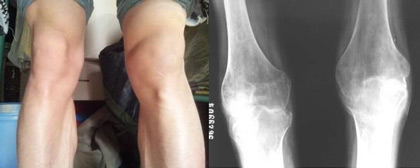

(图:刘虎治疗前的症状表现及ct显示)

来到成都风湿医院后,陈建春主任为刘虎进行系统规范的检查,检查报告显示刘虎C-反应蛋白26.15mg/L,血沉49mm/h,血小板450×10∧9/L,抗CCP抗体150RU/ml(正常参考值〈12RU/ml)。而且刘虎的膝关节开始肿胀,关节间隙狭窄,关节面边缘模糊不清,遭受到严重的破坏,凹凸不平或囊状透亮区,肘关节、膝关节肿胀,膝关节伸不直,脚踝关节活动受限。